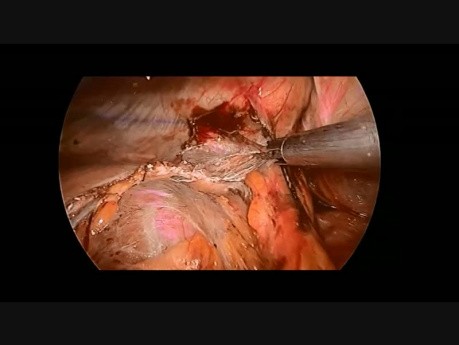

EMT laparoscópica con electrocauterio de gancho...

Historial médico: una mujer de 66 años (IMC 26,4) con adenocarcinoma de recto. Se sometió a radioquimioterapia neoadyuvante de larga duración. La TC preoperatoria reveló metástasis hepática en el segmento...